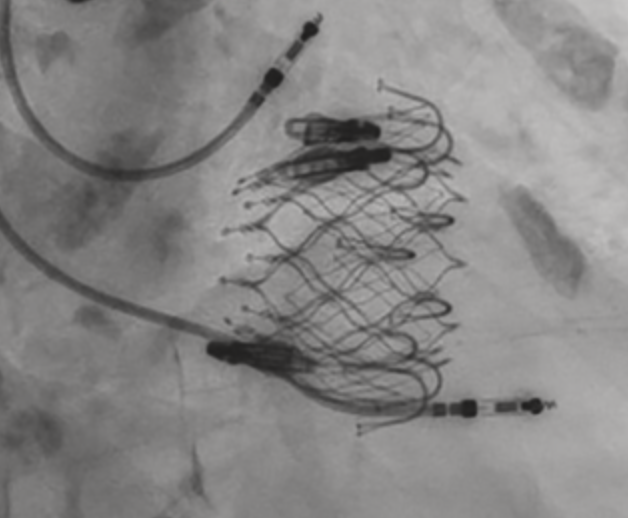

When your transseptal LV angiovac thrombectomy does not go as expected… but you are ready with the @ONOCORvascular in the ascending aorta 🙃

ŌNŌ helps again…

Great save by @CraigBasman and the team at Hackensack University Medical Center.

English

A nice save by the team at HUMC with Ono Retrieval..

@ONOCORvascular ,

Every high volume center should have this device on their shelf!

@vandanMD @PWengrofskyMD @SHYoonMD

#mitraclip

#structuralheart